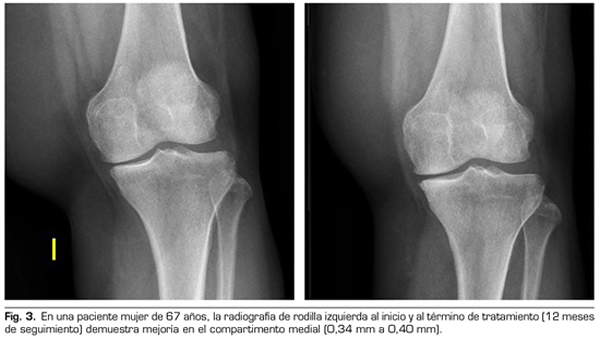

Variables radiológicas: en 53 pacientes analizados radiológicamente (según protocolo estandarizado) al año de seguimiento después del tratamiento con ozono, el compartimento interno aumento significativamente de 4.12 ± 1.41 mm a 4.4 ± 1.35 mm (p = 0.0008) y el compartimento externo aumentó de 6 ± 1.37 a 6.16 ± 1.4 mm (p = 0.0753).